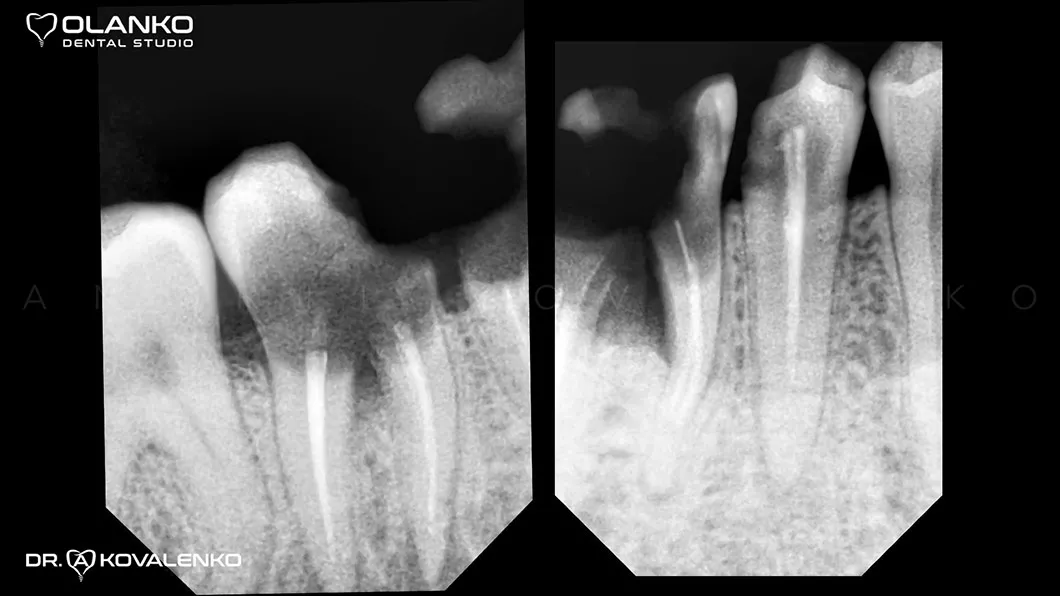

Пациент обратился с жалобами на боль и дискомфорт при жевании на нижней челюсти справа.

Лечение: удаление 2-х не подлежащих лечению зубов. Установка двух  имплантатов, с последующей установкой цельнокерамических коронок на индивидуальных абатментах.

Ситуация до

Клинический случай 4 имплантация зубов